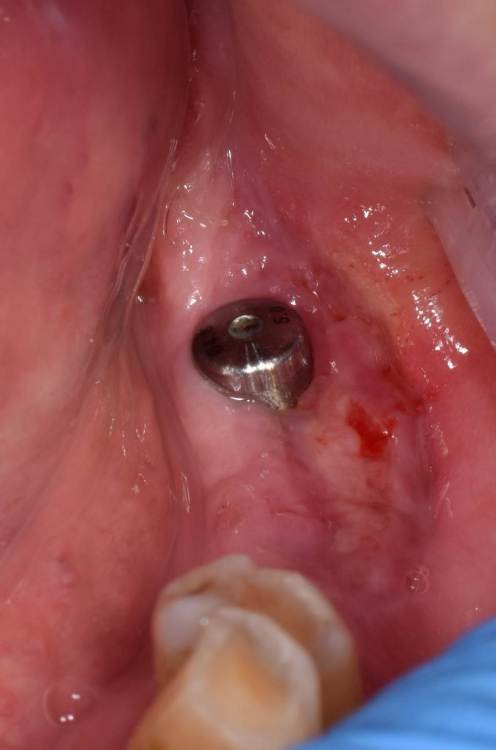

Fin Опубликовано 30 июня, 2023 Поделиться Опубликовано 30 июня, 2023 23.06.2023 в 20:47, Fin сказал: Коллеги. Подскажите какая самая частая проблема некроза СДТ. Уже много всего перепробовал. На 7 день вижу некроз. Раньше думал что очень много шью, и передавливаю. Потом думал что транспоантат очень толстый и сосуды не прорастают, но истончение СДТ не дало результата. На прошлой неделе пришил слабо, но все равно получил некроз.Вот не могу понять где проблема. Ма продолжение своих фотографий,-2 недели, вроде выжить что то должно. 1 Ссылка на комментарий